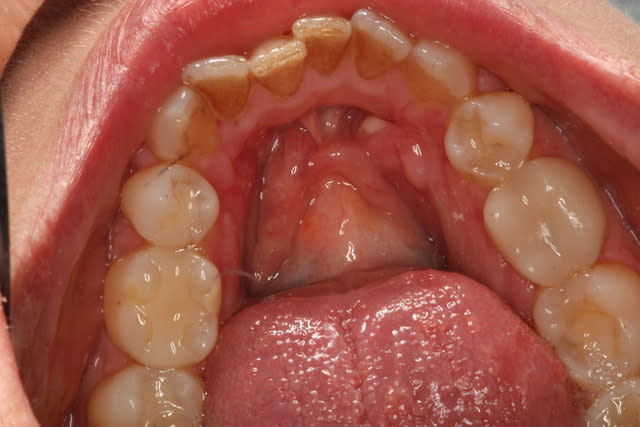

Demande de la patient qui avait souvent des ulcerations et qui avait la moitié de son repas qui restait coincé sous les tori. Elle consultait pour cela. On lui avait dit de "vivre avec".

Au final, l'indication était seulement de répondre à la demande très justifiée de la patient de retirer les toris. La patiente s'en porte très bien 18 mois plus tard.

Sur photo 3 et 4, on voit l'os exposé, après lambeau de décollement.

Incision sur le sommet des tori, incision de décharge en mésial.

Section osseuse en 3 blocs, puis remodelage de la zone avec pam droite et très grosse fraise ronde,

sutures (ablation de surplus de tissu mou au besoin)